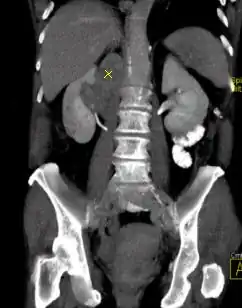

Computertomografie eines Knies, aufgenommen mit einem photonenzählenden CT. Schichtdicke ist 0,6 mm, mittleres CTDIvol ist 9,24 mGy

Bei allen bis zum Jahr 2021 eingesetzten Geräten trafen die Röntgenphotonen, nachdem sie den Patienten durchflogen haben, auf einen Kristall (z. B. aus Gadolinium-Oxysulfid), in dem sie in Photonen des sichtbaren Lichts umgewandelt wurden. In einer weiteren Stufe wurden sie vervielfältigt (Photomultiplier) und trafen anschließend auf eine Photodiode, welche das Licht in ein elektrisches Signal umwandelte, was dann ausgewertet wurde. Das elektrische Signal entspricht dabei einer Integration über alle Photonen (Energie-integrierender Detektor, EID), so dass Informationen zum Energiegehalt der einzelnen Photonen verloren gingen.

Bei einem quantenzählenden bzw. photonenzählenden Detektor entfällt der Umwandlungsschritt. Röntgenphotonen werden in den Halbleiterdetektoren direkt in einen elektrischen Strom umgewandelt, so dass die Information über ihren Energiegehalt erhalten bleibt. Als Detektormaterial können Cadmiumtellurid, Cadmiumzinktellurid oder Silicium benutzt werden. Korrekt implementiert bietet der Ansatz des Photon Counting CT (PCCT) den Vorteil einer mehr als doppelt so hohen räumliche Auflösung[35] sowie eine niedrigere Röntgendosis im Vergleich zu konventionellen Geräten. Auch können adipöse Patienten mit besserer Bildqualität untersucht werden. Durch einen geeigneten Schwellwert für die Energie der Photonen kann elektronisches Rauschen weitgehend herausgefiltert werden, was sich vor allem bei Untersuchungen mit niedriger Strahlendosis bemerkbar macht. Durch die Möglichkeit, die Energie der einzelnen Photonen zu kennen, ist eine Multispektral-Untersuchung ohne zusätzlichen Aufwand möglich.[36][37]